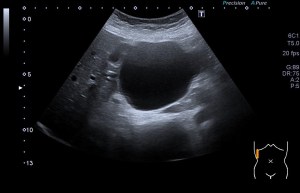

A la paciente se le pide la radiografía de ambos pies y la ecografía. La sospecha es el Juanete del Sastre. Esta afectación es una inflamación dolorosa de la cabeza del quinto metatarsiano.

La radiografía revela aumento de las partes y se refrenda en la ecografía como puedes ver en la imagen aunque aún no hay afectación en el hueso en el caso que te presento hoy.

Ecografícamente y debido a su levedad, en el caso de hoy solo observamos cambios en las partes blandas de la cara lateral de la cabeza del quinto metatarsiano, este tejido se muestra heterogéneo, la cortical del hueso ligeramente prominente sin afectación de la misma.